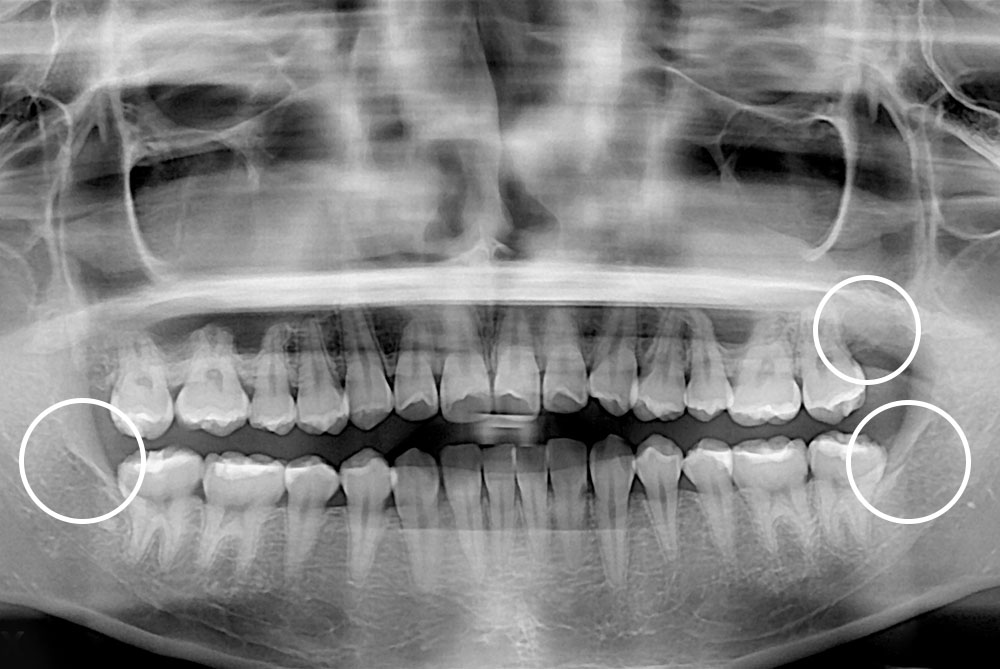

[사랑니] 매복 사랑니 발치

치료후 : 2019-01-30

세종치과는 구강악안면외과학 박사이신 원장님이 발치하는 치과입니다.